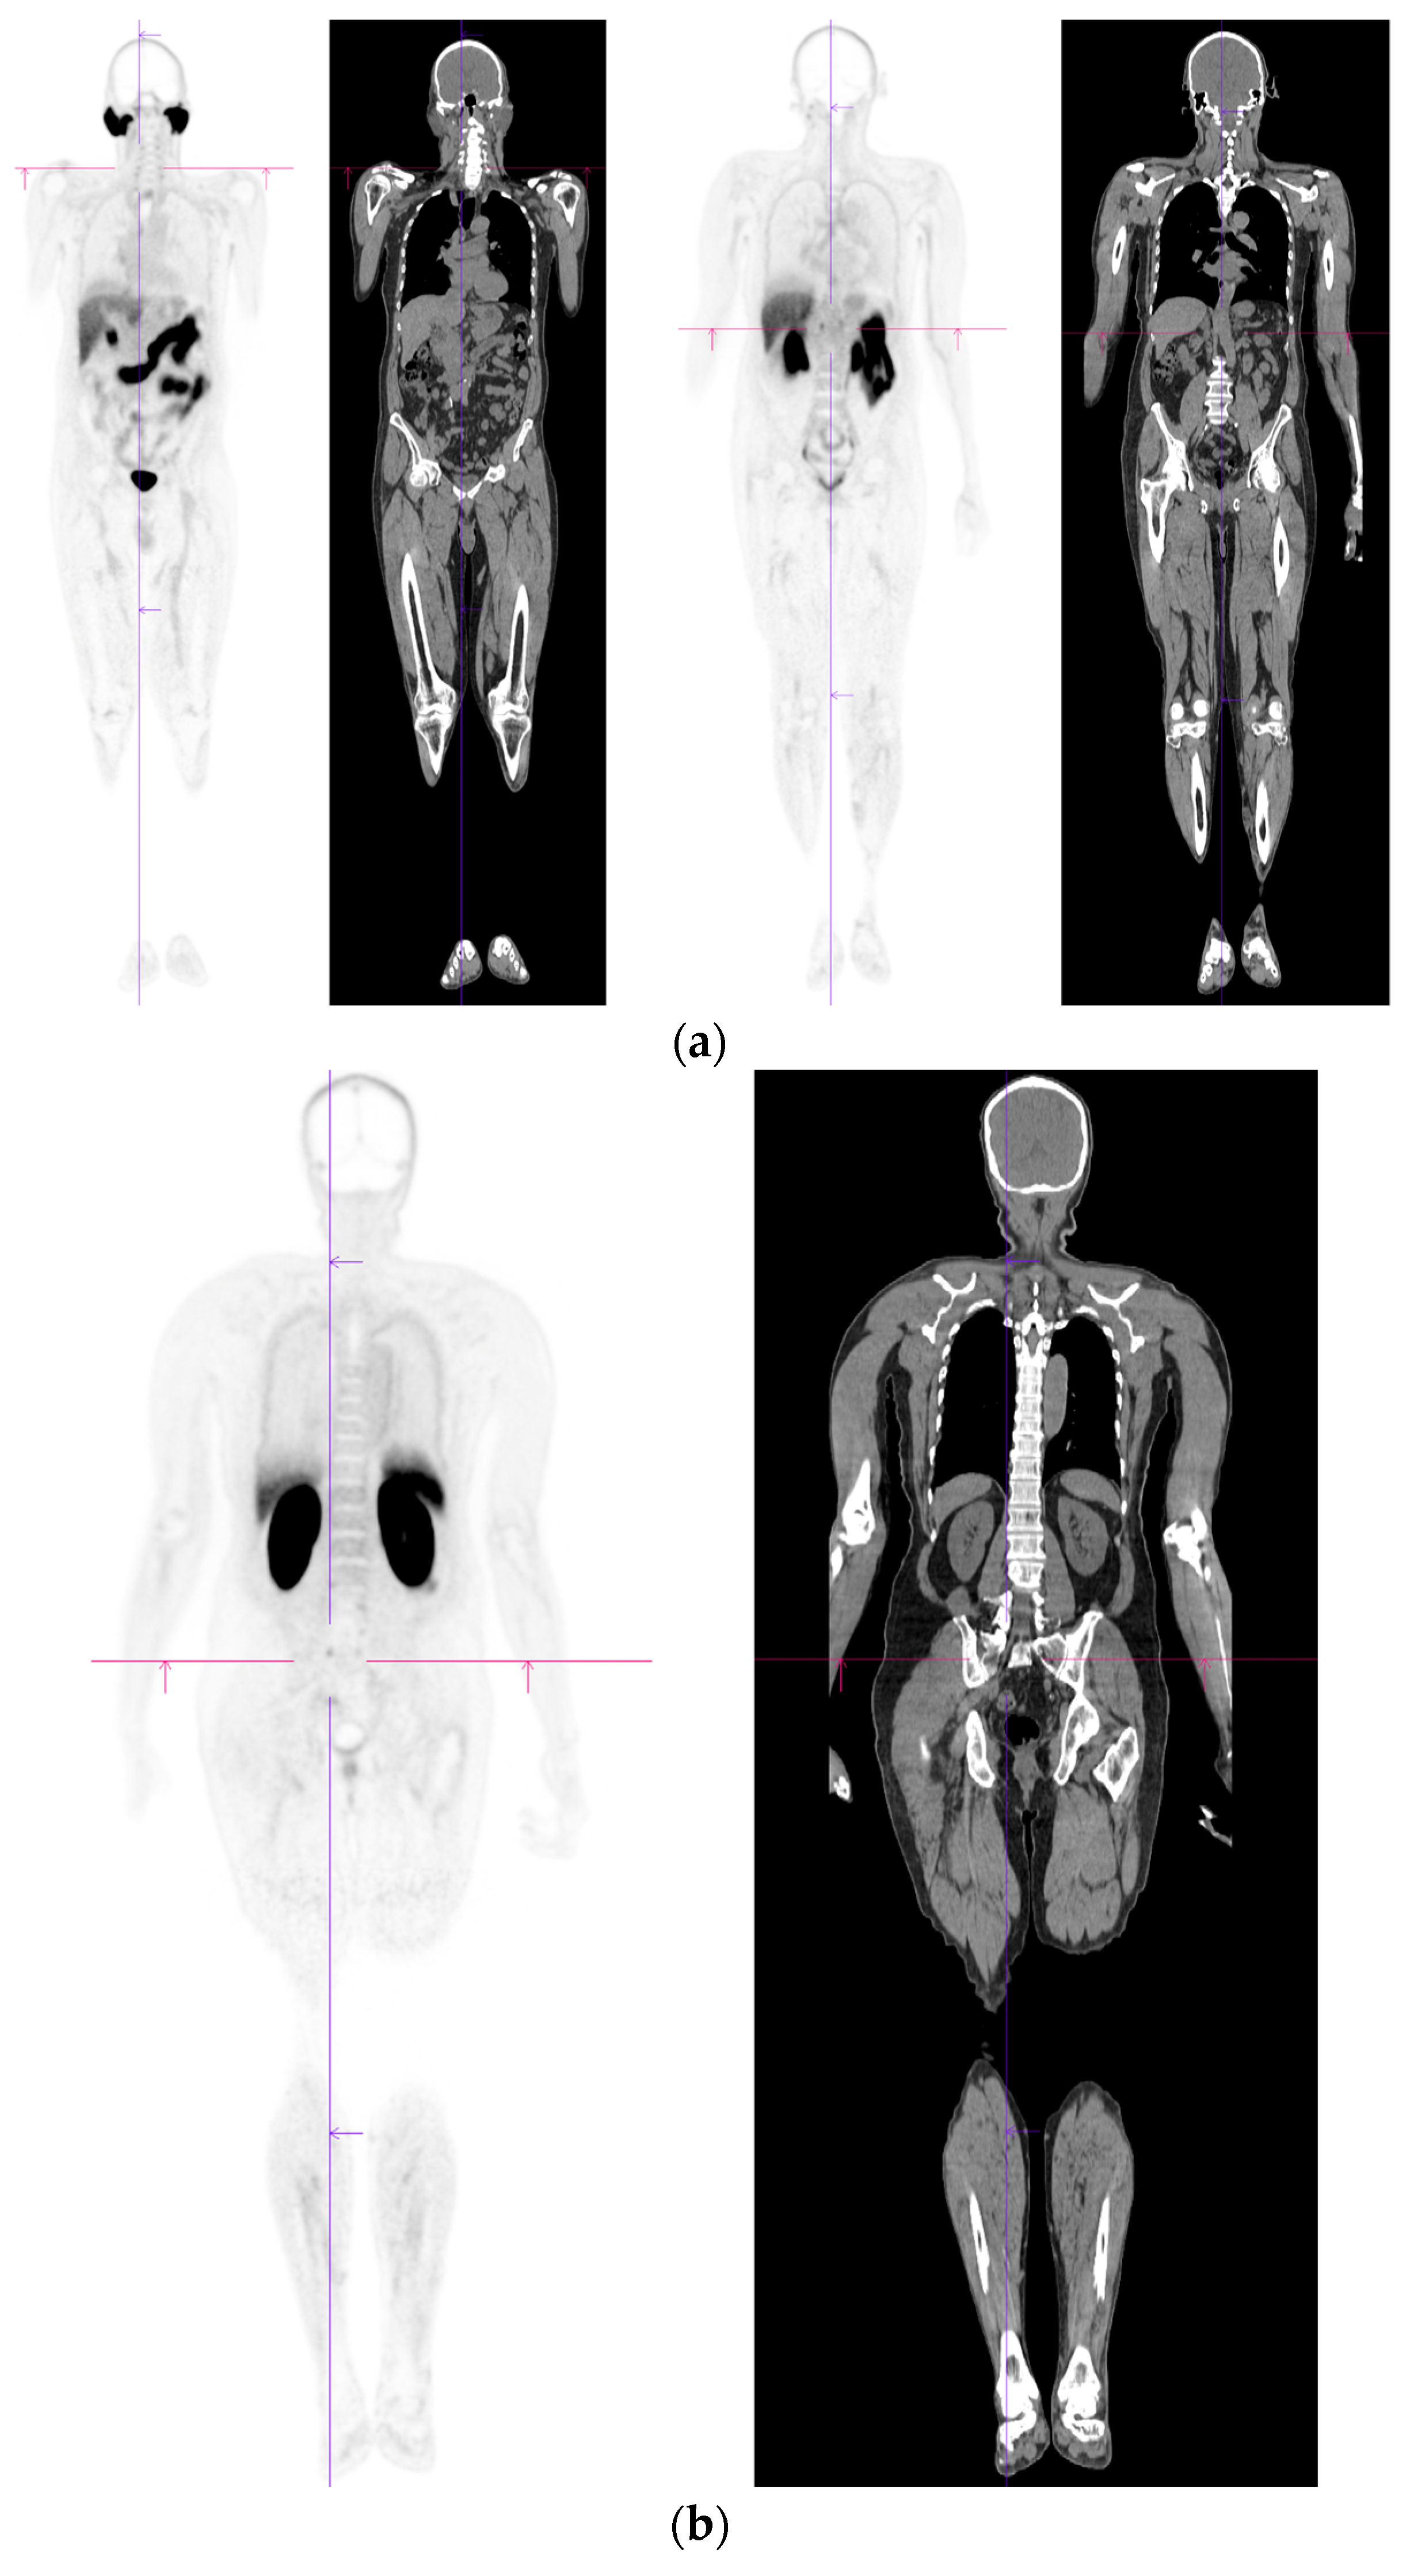

Figure 4.

Biochemical recurrence—serial scans. 58 yr old M—radical prostatectomy and node disSection 10 yrs prior; scans done in July 2020 when PSA 0.24 and Sep 2021 when PSA 0.38. (a): PSMA PET-CT: July 2020-68Ga-PSMA-226 MBq; uptake 49 min; BMI = 35.1; Wt 105 kg; coronal images and transaxial images at level of prostate bed show tracer excretion; rest of study clear. (b): PSMA PET-CT: Sep 2021-68Ga-PSMA-238 MBq; uptake 50 min; BMI = 35.2; Wt 107 kg; coronal images and transaxial images at level of prostate bed show tracer excretion but with a new small focus of uptake SUV= 6.0 in left side of prostate bed; rest of study clear.

Figure 5.

Biochemical recurrence—negative scan; normal distribution of tracer. 75 yr old M—radical prostatectomy 7 yrs prior; PSA 0.42. PSMA PET-CT: 68Ga-PSMA - 219 MBq; uptake 48 min; BMI = 22.6; Wt 63 kg. (a,b): coronal images show physiological uptake in parotid glands, bowel and kidneys and tracer pooling in bladder; X-hairs show uptake in cervical (SUV = 2.3) and sacral (SUV = 2.5) nerve roots and sympathetic ganglia in upper abdomen SUV = 4.6. (c,d): enlarged coronal, sagittal and transaxial images of prostate bed; X-hairs identify locations; no abnormal tracer uptake but pooling of trace in bladder problematic; Note—scale in sagittal images on (c) has been deliberately altered to ensure there are no adjacent focal regions of uptake to suggest local tumor recurrence.